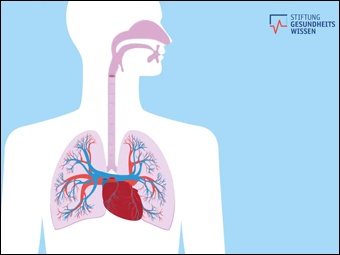

Wie funktioniert die Lunge?

(öffentlich)

Online-Medium

(2020)